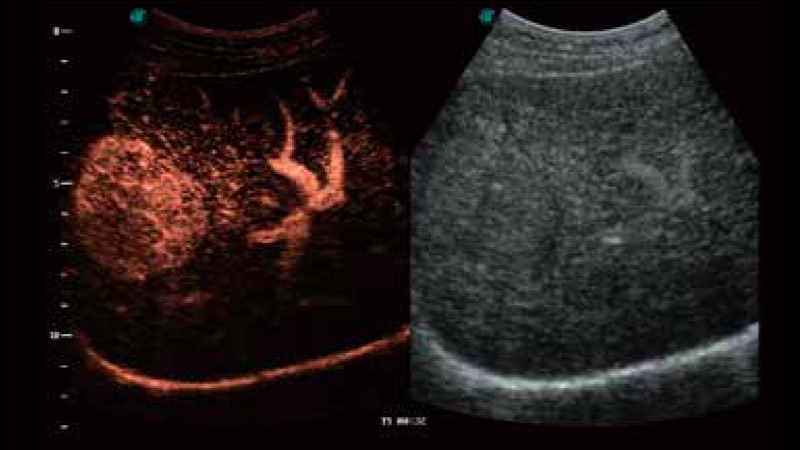

造影成像

造影成像功能和定量分析工具包使医生能够更好的评估血流灌注情况。独特的动态声压控技术有效控制造影剂的声压,保证更长的造影剂持续时间,更好的观察病变灌注的延迟相位。